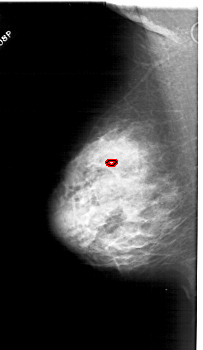

LEFT_MLO LINES 5941 PIXELS_PER_LINE 3436 BITS_PER_PIXEL 12 RESOLUTION 43.5 OVERLAY